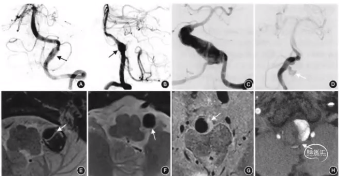

男,51岁,反复发作性面部疼痛5年,加重1周

DSA可见左侧椎动脉不规则瘤样扩张,近端狭窄。

HR-MRI

HR-MRI可见椎动脉夹层典型的双腔和壁间血肿。

术后DSA:

双支架双支架(SolitaireAB 6mm×30mm)辅助弹簧圈予以载瘤动脉血流重建;患者术后面部疼痛明显缓解。